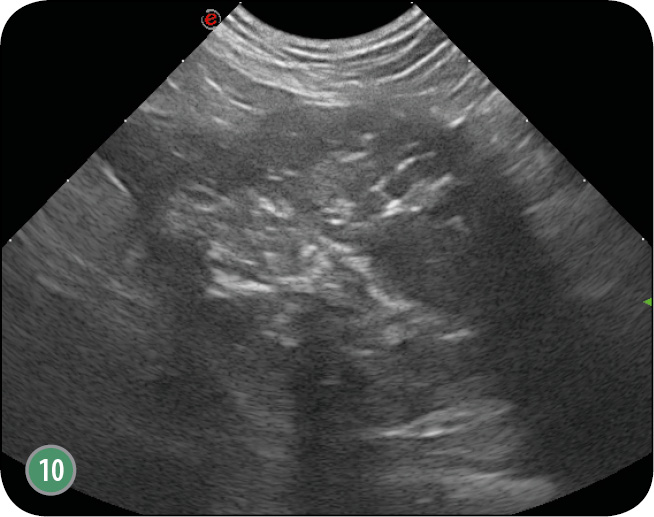

W obrazie ultrasonograficznym zmienionego nowotworowo gruczołu krokowego może wystąpić wiele zmian. Gruczoł zwykle ulega znacznemu powiększeniu, utkanie miąższu bywa często niejednorodne (ryc. 8), występują hiper- i hipoechogeniczne obszary (ryc. 9) (1, 4, 7, 12, 16, 21, 26, 30). Obserwuje się również zmiany jamiste o szorstkich krawędziach, zmiany lite o utkaniu tkankowym, jedno- lub wieloogniskowe (ryc. 4b). Nierzadko widoczne są hiperechogenne echa z cieniem akustycznym, które świadczą o obecności zwapnień (ryc. 10).